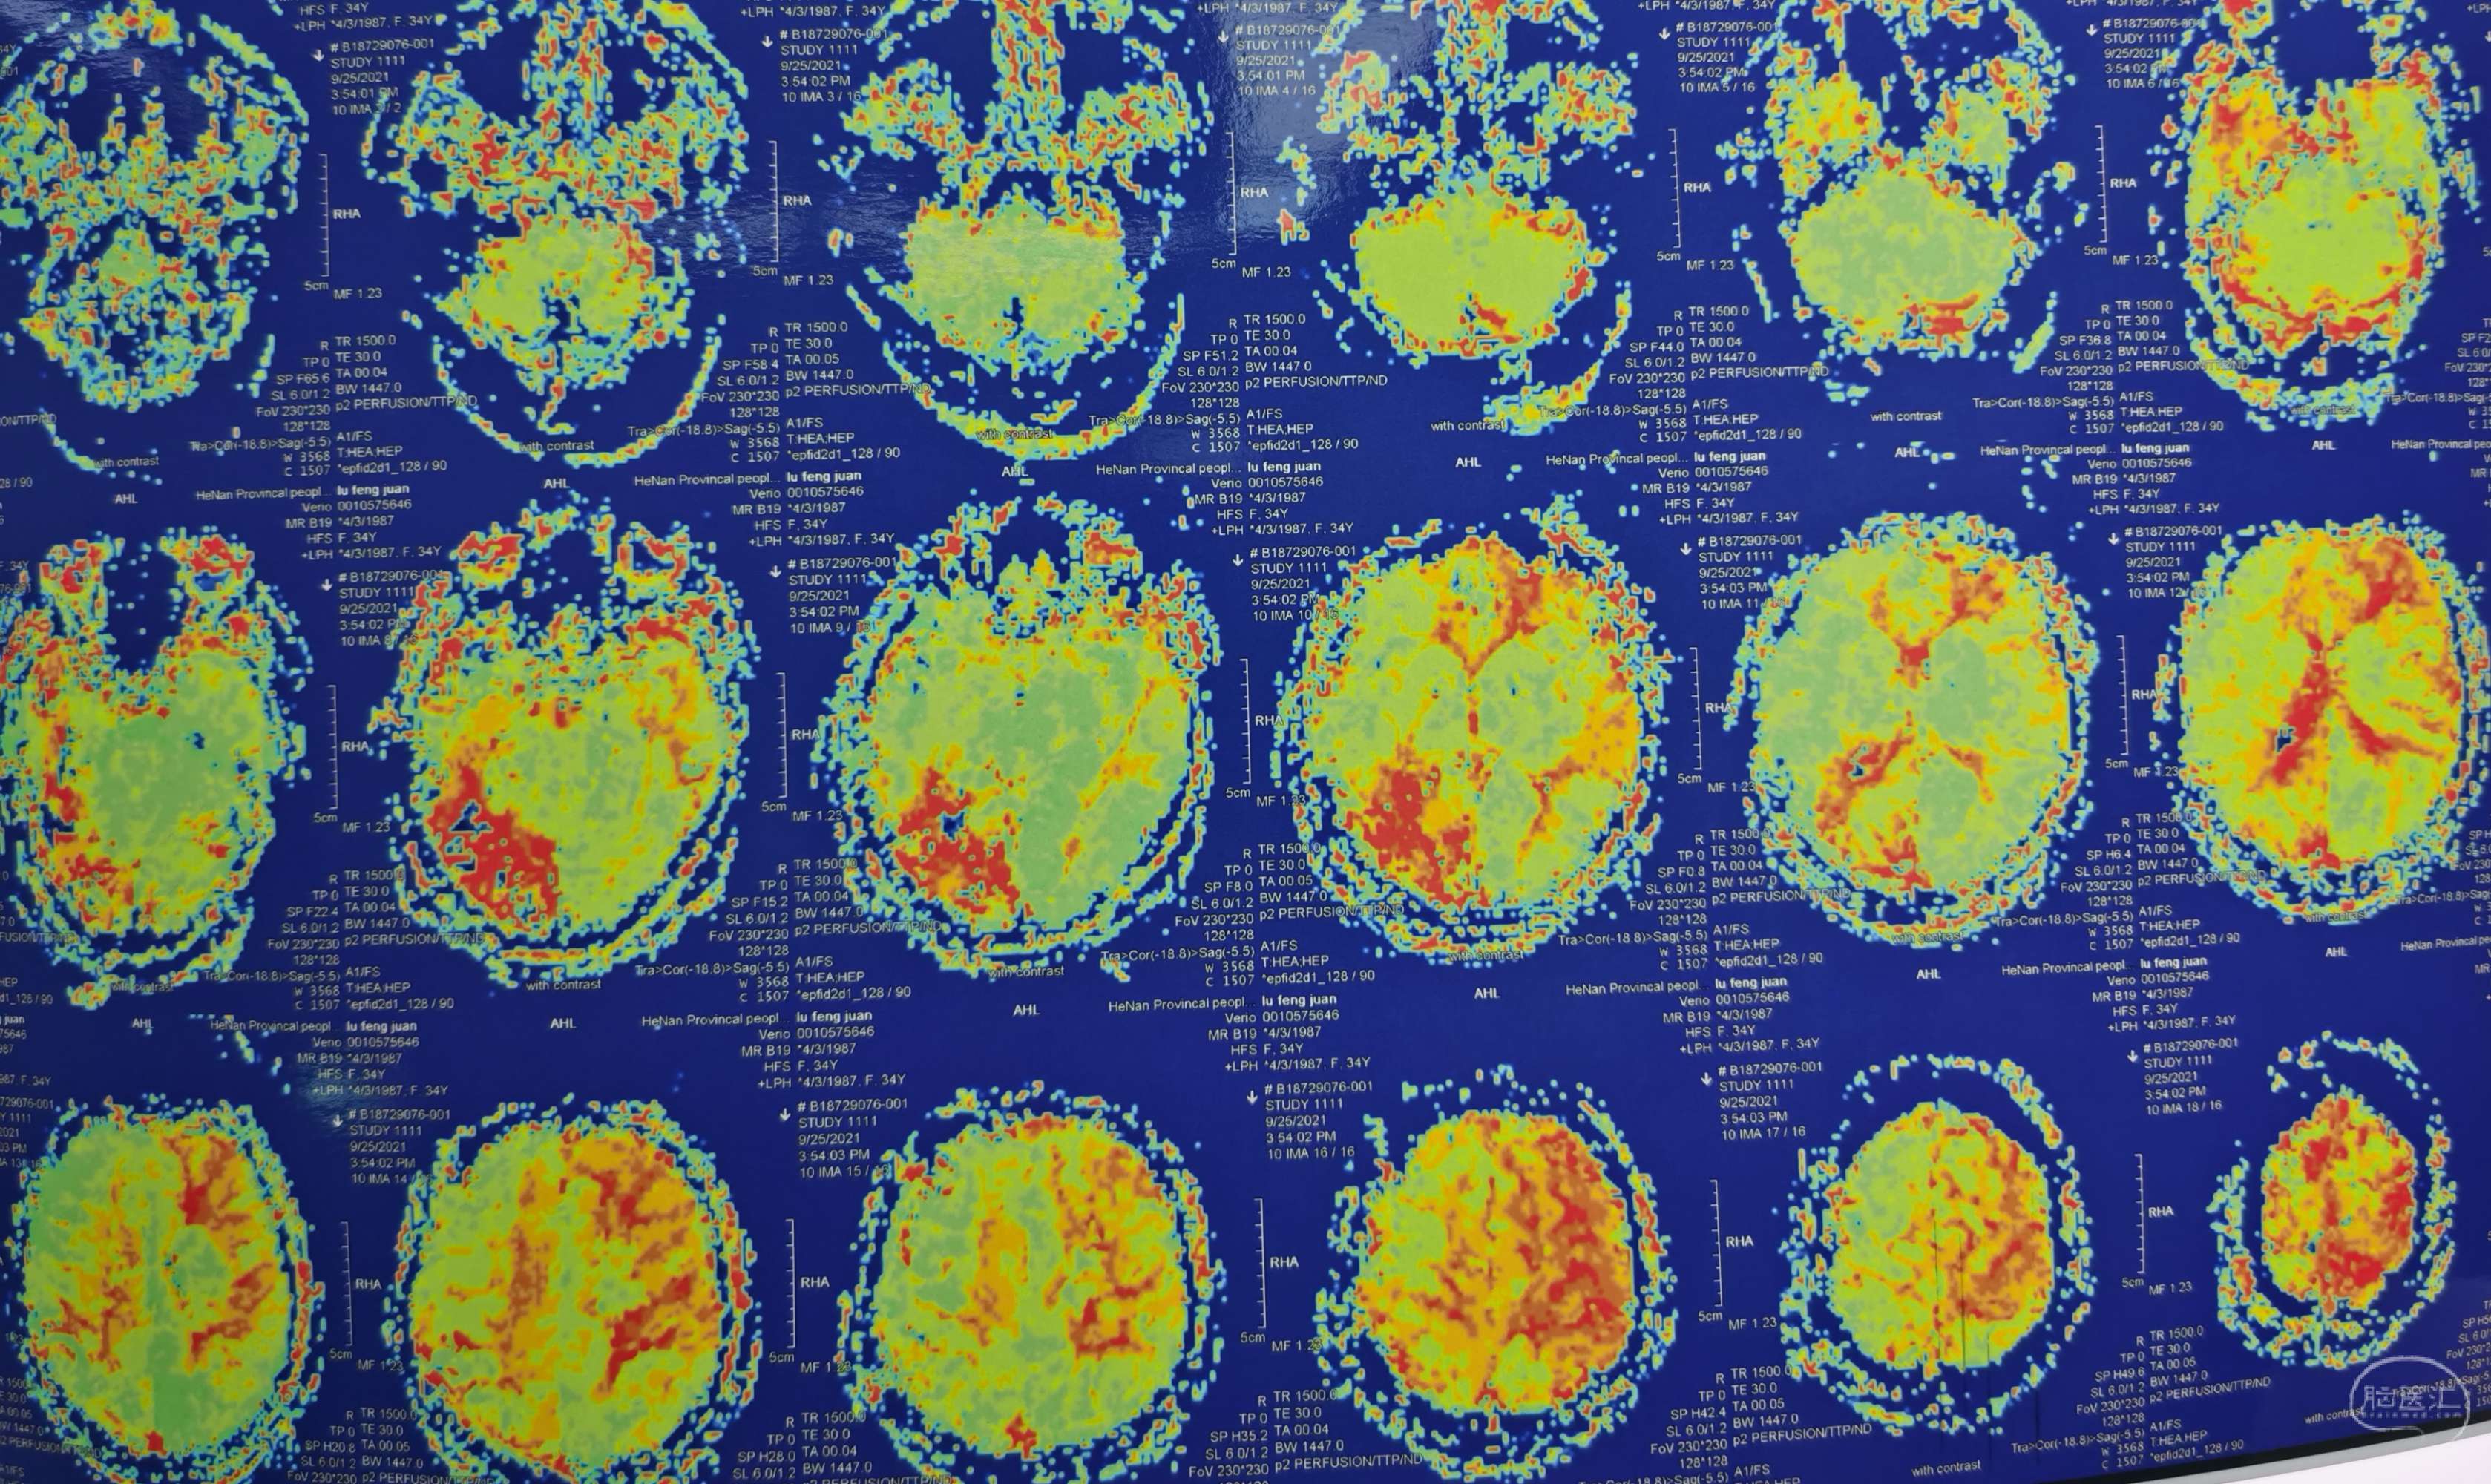

磁共振灌注提示:左侧大脑半球低灌注改变。

磁共振灌注提示:双侧大脑半球低灌注改变。